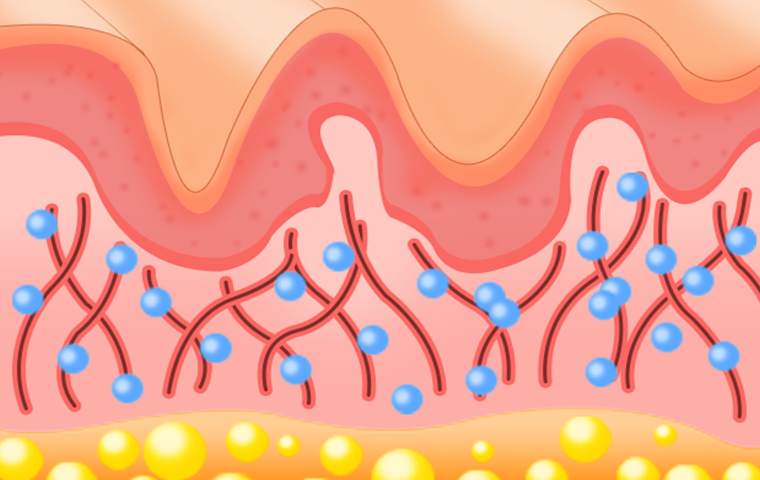

쥬베룩은 PDLLA와 히알루론산이 결합된 제품으로

자가 콜라겐 생성을 유도하는 주사 시술입니다.

즉각적인 볼륨을 만드는 필러와 달리, 피부 속 콜라겐 생성을 유도하여

시간이 지날수록 자연스러운 '나만의' 볼륨을 형성합니다.

부위의 진피와 지방조직 사이에 주입합니다.

PLA성분이 분해되면서 콜라겐 등의

신생조직 생성을 촉진합니다.